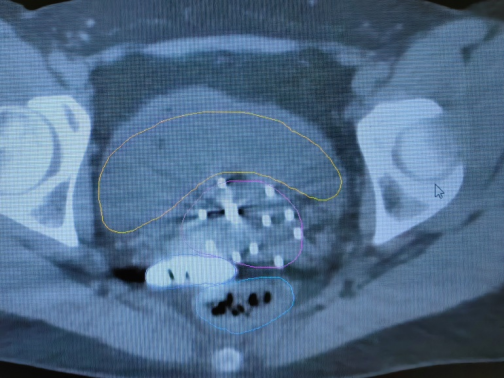

2. 無痛近距離插植治療:近距離插植治療是將宮腔管和插植針等施源器的置入宮頸及宮旁病灶組織的一種放療方式,由于老年患者陰道狹窄、對疼痛耐受性差,很多難以配合治療,甚至拒絕治療,導(dǎo)致腫瘤無法得到根治。我院婦科放化療采取靜脈麻醉下給予患者無痛插植治療,能夠最大程度上減少治療過程中患者的疼痛感和恐懼感,使得治療得以順利進(jìn)行,避免因中斷治療帶來的劑量缺陷,提高患者腫瘤的局部控制率,極大提高患者治療舒適度及依從性。

*無痛插值靶區(qū)